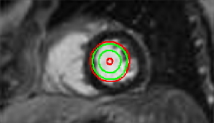

Refer to captionRefer to captionRefer to captionRefer to captionRefer to captionRefer to captionRefer to captionRefer to captionRefer to captionRefer to captionRefer to captionRefer to caption\begin{array}[]{cc}\includegraphics[width=112.0187pt]{lv-2-init.pdf}&\includegraphics[width=112.0187pt]{lv-2.pdf}\\ \includegraphics[width=112.0187pt]{lv-3-init.pdf}&\includegraphics[width=112.0187pt]{lv-3.pdf}\\ \includegraphics[width=112.0187pt]{lv-1-init.pdf}&\includegraphics[width=112.0187pt]{lv-1.pdf}\\ \end{array}

Figure 15: Segmentation of left ventricle wall of the heart in an MR image taken from [42]. Left column shows initialization and right column shows converged result.

We next develop templates for objects with hole(s) in their structure. These templates are called ring templates. Figures 15 and 16 show examples of ring templates. The area enclosed between the red contours act as region 1subscript1\Re_{1} and the area between the green contours is region 0subscript0\Re_{0}. Figure 17 shows the construction of the ring contours. The two seemingly unconnected contours are actually one connected contour. Hence, partial derivative calculations in equation (26) are still valid.

In Figure 15, the ring template has been used for segmenting the left ventricular (LV) wall of heart in cardiac MR images. Another example is shown in Figure 16. The template used in both examples has a greater thickness in the inner ring-shaped annular region than the outer annular region. This was done to facilitate obtaining the desired object’s structural information by means of the contrast (for example, between the endocardium and the LV wall) that a good initialization can offer. Hence, while designing a template, we can incorporate prior knowledge of the object and its surroundings.